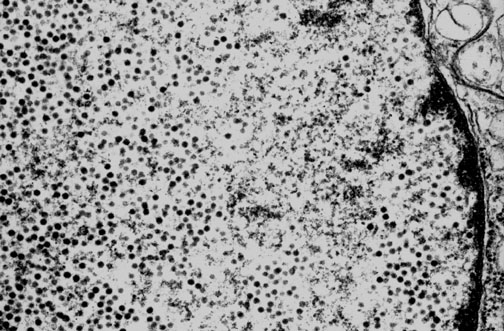

Progressive multifocal leukoencephalopathy is caused by infection with the JC papovavirus. Here, small round dark JC viral particles appear in the nucleus of an infected oligodendrocyte in this electron micrograph.